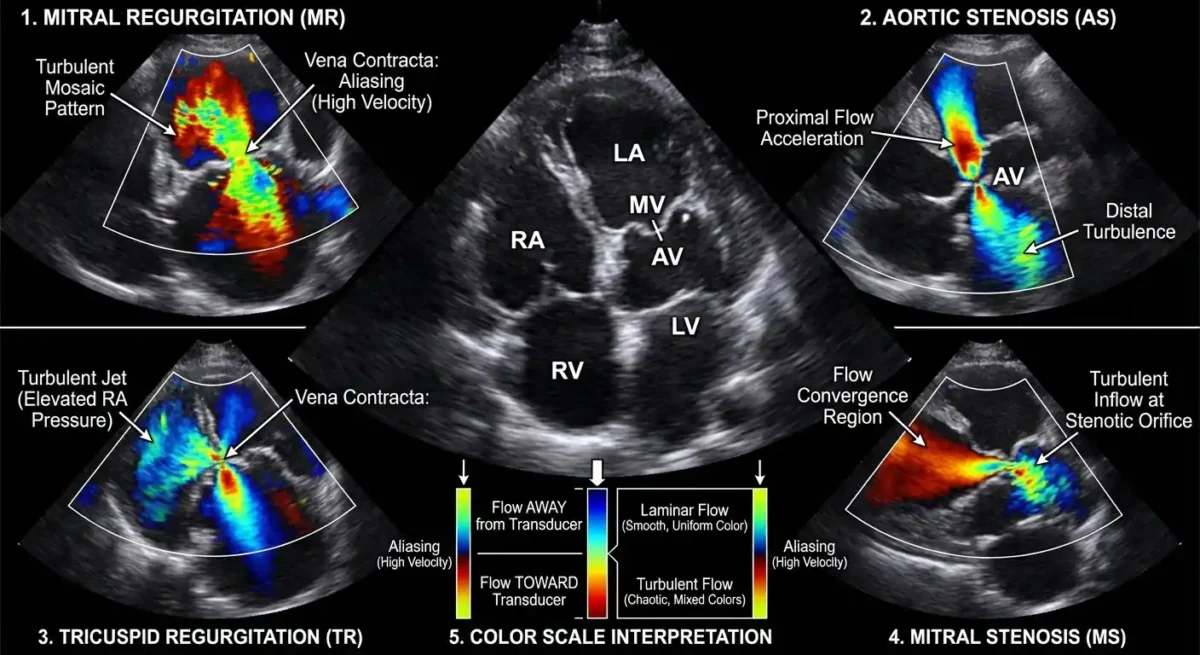

در این روش، دستگاه اکو با استفاده از کدگذاری رنگی، جریان خون را روی تصویر قلب نمایش میدهد. معمولاً رنگ قرمز نشاندهندهٔ جریان به سمت پروب و رنگ آبی نشاندهندهٔ جریان دور از پروب است. رنگهای ترکیبی مانند زرد و سبز نیز میتوانند نشانهٔ سرعتهای بالا یا جریانهای آشفته باشند. این نمایش رنگی به پزشک کمک میکند تا الگوهای جریان را در یک نگاه تشخیص دهد و ناهنجاریها را سریعتر شناسایی کند.

در این روش، رنگها معنایی فیزیکی و دقیق دارند. جریان خونی که بهسوی پروب حرکت میکند، معمولاً با رنگهای گرم—اغلب قرمز—نمایش داده میشود و جریان دورشونده با رنگهای سرد—عمدتاً آبی. این تقسیمبندی، نه قراردادی دلخواه، بلکه بازتابی از تغییر فرکانس امواج بازتابشده است. هرچه سرعت جریان بیشتر باشد، شدت رنگ نیز افزایش مییابد و طیفی از رنگهای روشنتر یا تیرهتر پدید میآید. بدینسان، رنگها نهتنها جهت، بلکه شدت جریان را نیز بازمیتابانند.

اما تفسیر رنگها تنها به تشخیص جهت و سرعت محدود نمیشود. یکی از پدیدههای مهم در داپلر رنگی، Aliasing است؛ حالتی که در آن سرعت جریان از حد قابل اندازهگیری دستگاه فراتر میرود و رنگها بهصورت وارونه یا موزاییکی دیده میشوند. این پدیده، هرچند در ظاهر نوعی اختلال است، اما در بسیاری موارد نشانهای از جریانهای پرسرعت و غیرطبیعی است؛ مانند نارسایی شدید دریچهای یا تنگیهای مهم. پزشک آگاه، این وارونگی رنگ را نه خطا، بلکه نشانهای بالینی میداند و آن را در تحلیل خود بهکار میگیرد.

جریانهای آشفته یا Turbulent Flow نیز در داپلر رنگی جلوهای خاص دارند. این جریانها، که معمولاً در اثر تنگیها، ناهنجاریهای مادرزادی یا نارساییهای شدید پدید میآیند، با رنگهای درهمتنیده و موزاییکی نمایش داده میشوند. این آشفتگی رنگی، بازتابی از بینظمی سرعت و جهت خون است و میتواند پزشک را به وجود اختلالی مهم در مسیر جریان رهنمون سازد. در مقابل، جریانهای طبیعی و آرام، الگویی یکنواخت و همگن دارند و رنگها در آنها بهصورت منظم و پیوسته دیده میشوند.

در دریچهها، هر رنگ و هر الگو معنایی خاص دارد. در دریچهٔ میترال، جریان طبیعی در زمان دیاستول بهسوی بطن چپ است و با رنگی مشخص دیده میشود. هرگونه جریان بازگشتی در زمان سیستول، که با رنگی مخالف ظاهر میشود، نشانهٔ نارسایی است. در دریچهٔ آئورت، جریان طبیعی در زمان سیستول بهسوی آئورت است و هر جریان معکوس در دیاستول، نشانهٔ نارسایی آئورت. این الگوهای رنگی، همچون امضایی برای هر بیماریاند و پزشک با شناخت آنها میتواند شدت و ماهیت اختلال را دریابد.

🚪ارزیابی بیماریهای دریچهای با اکو داپلر رنگی

بیماریهای دریچهای قلب، چه از نوع نارسایی و چه از نوع تنگی، از مهمترین اختلالاتی هستند که میتوانند ساختار و عملکرد قلب را دگرگون سازند. اکو داپلر رنگی در این میان، همچون چشمی تیزبین و آگاه، جریان خون را در گذر از دریچهها مینگرد و کوچکترین بینظمی را آشکار میسازد. این روش، با ترکیب تصویر آناتومیک و اطلاعات همودینامیک، امکان تشخیص دقیق و درجهبندی اختلالات دریچهای را فراهم میکند و نقشی اساسی در تصمیمگیری درمانی ایفا مینماید.

در نارسایی دریچهای، داپلر رنگی نخستین ابزاری است که وجود جریان بازگشتی را آشکار میکند. در حالت طبیعی، خون باید تنها در یک جهت از دریچه عبور کند؛ اما هنگامی که دریچه بهدرستی بسته نشود، بخشی از خون در زمان نامناسب به عقب بازمیگردد. این جریان بازگشتی، در داپلر رنگی بهصورت جریانی باریک یا گسترده با رنگی مخالف جریان طبیعی دیده میشود. شدت و وسعت این جت بازگشتی، سرنخهایی ارزشمند دربارهٔ درجهٔ نارسایی بهدست میدهد. پزشک با مشاهدهٔ طول، پهنا، تراکم رنگ و میزان نفوذ جریان به حفرهٔ مقابل، میتواند شدت نارسایی را از خفیف تا شدید طبقهبندی کند.

در تنگی دریچهها نیز داپلر رنگی نقش مهمی دارد. تنگی، گذرگاه طبیعی خون را باریک میسازد و جریان را وادار میکند با سرعتی بیشتر از میان دریچه عبور کند. این افزایش سرعت، در داپلر رنگی بهصورت جریانی تند و متمرکز دیده میشود که اغلب با پدیدهٔ Aliasing همراه است. این الگوی رنگی، همچون نشانهای روشن، وجود تنگی را اعلام میکند و پزشک را به انجام ارزیابیهای دقیقتر با داپلر طیفی رهنمون میسازد. در دریچهٔ آئورت، این جریان پرسرعت در زمان سیستول دیده میشود و در دریچهٔ میترال، در زمان دیاستول.

دریچهٔ تریکوسپید و پولمونری نیز از نگاه داپلر رنگی پنهان نمیمانند. نارسایی تریکوسپید، که اغلب در بیماران با فشار خون ریوی دیده میشود، با جتی بازگشتی بهسوی دهلیز راست ظاهر میشود. این جریان، افزون بر تشخیص نارسایی، در تخمین فشار شریان ریوی نیز کاربرد دارد. در دریچهٔ پولمونری، داپلر رنگی میتواند نارسایی یا تنگی را با دقتی مشابه آشکار سازد.